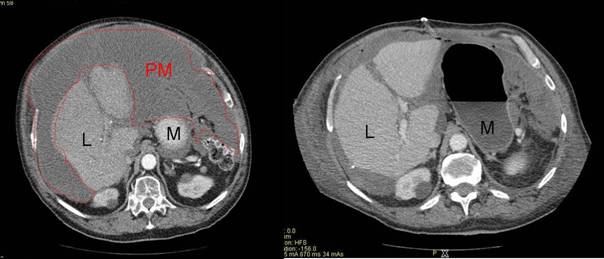

Zielsetzung der Operation ist es alle sichtbaren Tumormanifestationen aus dem Bauchraum zu entfernen, um möglichst gute Voraussetzungen für die Wirksamkeit der intraperitonealen Chemotherapie zu schaffen. Die Operation gliedert sich dabei in zwei Phasen. Im ersten Teil der Operation werden die größeren Tumorformationen entfernt (Abbildung 2), wobei bestimmte unter Umständen Organanteile wie z.B. Teile des Darmes mit reseziert werden müssen.

Abbildung 2 : Computertomographie mit einem ausgedehnten Pseudomyxoma peritionei (PM) mit Verdrängung von Magen (M) und Leber (L) vor und nach operativem Tumordebulking |